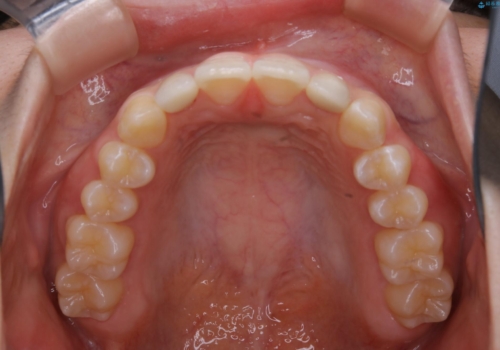

- 初診時、前歯部の見た目の改善を主訴にご来院されました。生まれつき歯が小さい状態の「矮小歯」とそれに伴う正中の「すきっ歯」があるため、大きなガタつきはないものの笑った時の印象に違和感が出る状態となっていました。

矮小歯が傾斜していることなどを踏まえ、より安全に治療を進めるために部分矯正を併用したセラミッククラウンでの治療を行うこととなりました。

今回のケースでは、歯が小さいだけでなく傾斜もしていたため補綴治療時に歯を削ることで神経の症状が出る可能性がありました。そのため、事前に部分矯正を行い歯軸の改善を行っておくことで、歯髄を温存することができました。